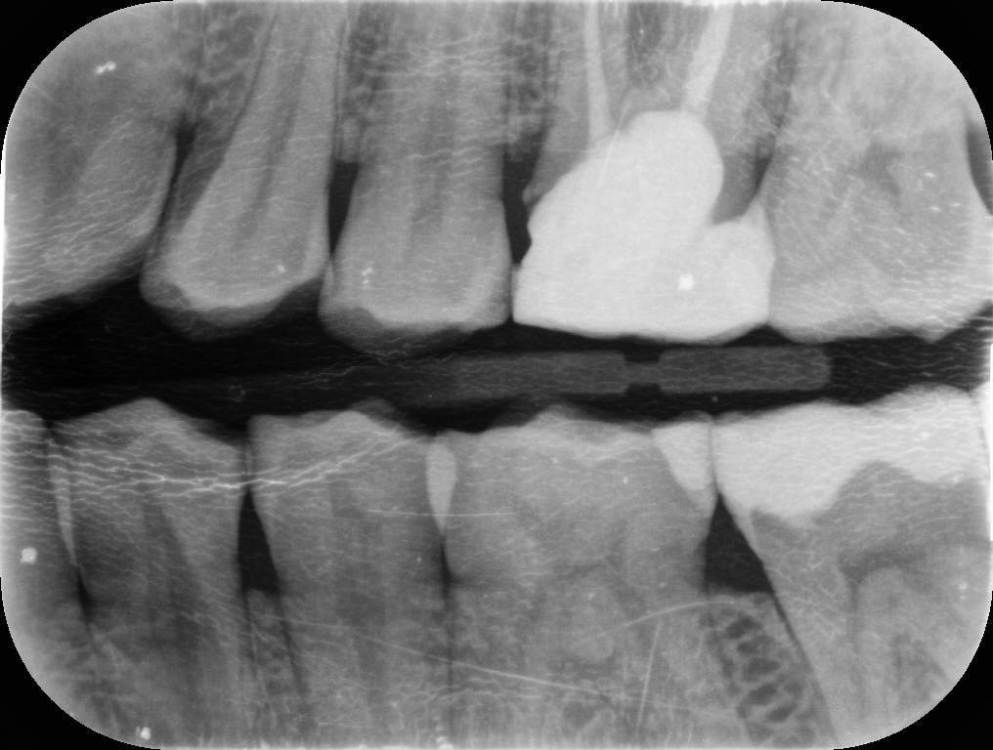

randomsctions Опубликовано 21 апреля, 2023 Поделиться Опубликовано 21 апреля, 2023 (изменено) Здравствуйте! Около 10 дней назад появилась стреляющая боль в верхней части челюсти слева. Сходил ко врачу (терапевту), результат: боли неясного характера. выписали дексаметазон и сказали наблюдать. На время стало меньше болеть. два дня назад сильно заболело в области, обведенной красным на снимке. Сначала казалось, что это зуб с большой пломбой, теперь, спустя два дня непрерывной интенсивной боли уже тяжело сказать, откуда именно исходит боль. Болит очень сильно, на 9 точно, почти невозможно терпеть. Не спал двое суток, и непонятно, когда удастся. Принимал по несколько таблеток кетарола, кетанова и ибупрофена, почти никакого эффекта, уснуть невозможно. вчера посетил утром другого врача (т.к. у первого не было номерков) - сделали снимок, сказали, точно не могут определить, с каким зубом проблема, и не хотят просто так пломбировать каналы здоровых зубов. Сказали, что боль может иррадиироваться от восьмёрок, и их можно попробовать удалить, но тоже не факт, что поможет. Выписали непраксен и антибиотики на 5 дней, записали на следующую неделю. Боль нестерпимая, поэтому в этот же день пошел в третью клинику. Надеялся, что удалят две восьмерки слева, и если боль не пройдёт, то уже смотреть дальше. Но врач отказалась удалять что-либо, а сказала, что 99%, что из-за стирания эмали и оголения дентина у зубов повысилась чувствительность, и отсюда боль (бруксизм у меня действительно есть, и зубы сильно стёрты, и часто реагируют на температуру или даже прикосновения). Покрыли сразу много зубов раствором для пломб, и отправили домой. В течение 2-3 часов я не чувствовал боль из-за анестезии (это были лучшие два часа за всё это время). Но сразу после этого разболелось ещё сильнее. Я уже не знаю, как мне это пережить, т.к. боль такая, что абсолютно невозможно уснуть. Уже готов удалить любое количество зубов, лишь бы избавиться от боли. Но если считать 4 обведенных красным зуба плюс пятый — 8ка снизу, то, как я понимаю, сразу 5 зубов удалять никто не станет. очень прошу подсказать, что тут можно сделать. Если это не решится за максимум ещё два дня, я не знаю, как я буду дальше. Не спать пятые сутки уже будет невозможно. Я готов удалить зуб(ы), но какой? Изменено 21 апреля, 2023 пользователем randomsctions Дополнение про бруксизм Ссылка на комментарий